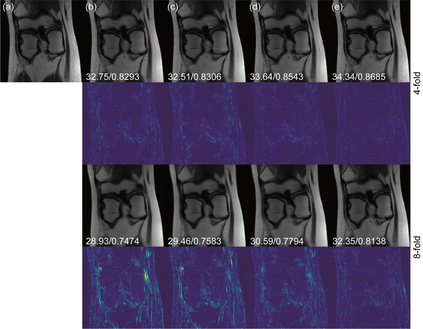

Deep learning-based MRI reconstruction models have achieved superior performance these days. Most recently, diffusion models have shown remarkable performance in image generation, in-painting, super-resolution, image editing and more. As a generalized diffusion model, cold diffusion further broadens the scope and considers models built around arbitrary image transformations such as blurring, down-sampling, etc. In this paper, we propose a k-space cold diffusion model that performs image degradation and restoration in k-space without the need for Gaussian noise. We provide comparisons with multiple deep learning-based MRI reconstruction models and perform tests on a well-known large open-source MRI dataset. Our results show that this novel way of performing degradation can generate high-quality reconstruction images for accelerated MRI.